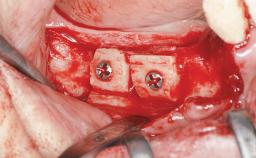

Iliac and Calvarial Bone Blocks for Onlay Grafting of a Severely Resorbed Edentulous Maxilla

Bone Augmentation Horizontal|Sinus Floor Elevation|Staged|Vertical

Augmentation Materials Autogenous chips|Autogenous block(s)

Bone Volume Deficient vertically or deficient vertically AND horizontally